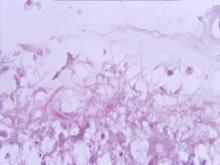

各臟器呈現多數大小不等之肉芽腫結節病變,即該病灶之肉芽腫中心有大量細菌及壞死組織及少量炎症細胞,並有明顯數層類上皮細胞包圍。 2.

抗酸染色在肉芽腫周區有紅色念珠樣弱抗酸菌。 3.

免疫化學染色在肉芽腫病灶區呈現黃棕色陽性反應。 四、 實驗室檢驗: 1.